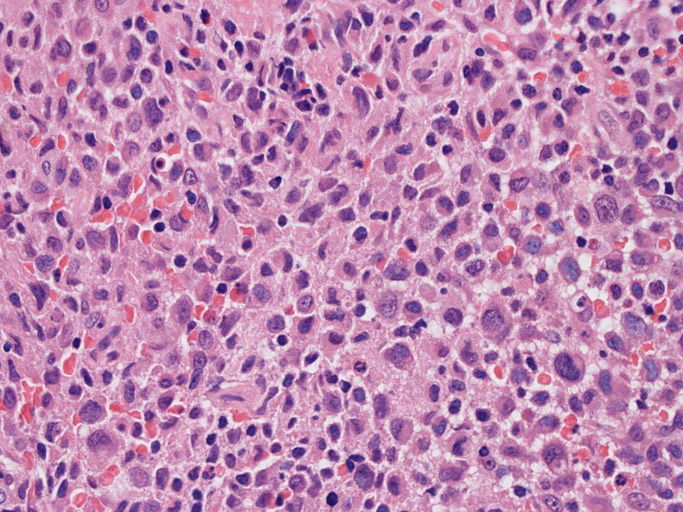

LCSの病理組織所見

Langerhans cell histiocytosisの高悪性度 variantで明らかな悪性像を示すLangerhans cellの腫瘍性増殖と定義される(WHO, 2008)

大型細胞の増殖よりなる腫瘍。縦溝,しわ,切れ込みのある核をもった大型細胞も出現する。クロマチンは顆粒状で核小体も明瞭である。核分裂は >50/10hpfと多い。eosinophilsは少ない。壊死が多発することがある。未分化ないし低分化な細胞像, 組織所見のため鑑別診断は多岐にわたり、的確な免疫染色を行う必要がある。

皮膚に異型細胞の浸潤がみられる。異型細胞は表皮内に浸潤するほか、表皮真皮境界部, 真皮, 皮下脂肪組織にもびまん, 結節様の浸潤所見を示す。血管周囲に浸潤、集蔟する所見も多く見られる。 増殖浸潤細胞の核には類円形や腎臓形, またはへこみ, 切れ込み, 溝などを有する多型な核が認められる。クロマチンは粗でvesicularな核が多い。核小体の明らかな核もある。好エオジン性の核内封入体様構造も少数に見られた。mitosisは容易に認められる。hyperchromaticな多型核, bizzarreな細胞が高頻度に認められ異型度は高いと考えられる。細胞質は境界不明瞭, 淡明または泡沫様の 好エオジン性胞体である。

免疫染色 浸潤細胞はCD1a+, S100+, Langerin+, HLA-DR+, CD4+, CD45+, CD68+. MIB-1 index:24.4%